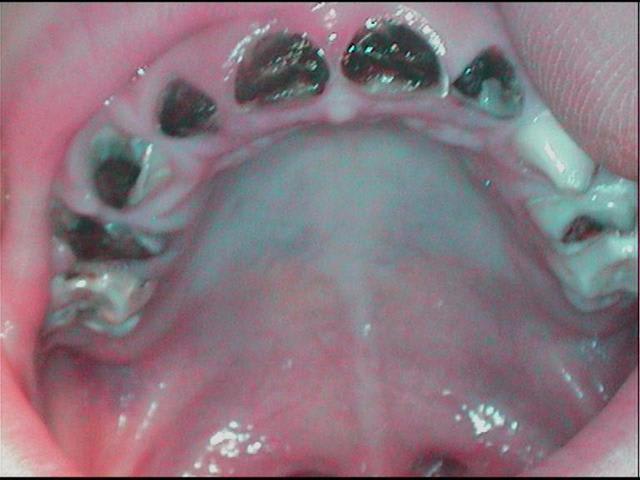

petit bout de chou tout mignon tout gentil mais tout un cinoche pour faire des photos...

pas manqué de biberon sucré visiblement

5ans....pfff...par quoi on commence...

la camera suffit bien pour montrer cela,mais meme pas le temps pour ajuster, zoomer etc...

et sous le meuble ou il était réfugié c'est pas si mal

personnellement pas de frustration a ne pas voir mieux les menus details...

tres "beau" cas

14 dents a traiter a 5 ans et des parents criminels a eduquer( freres et soeurs?),normal que tu te sentes un peu depasse

ps:elles sont pas si mal tes photos :)